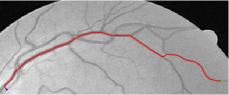

Compare to existing minimal path models. The Riemannian metrics used in [1, 4, 5] are based on the local pointwise information. The curvature-penalized metric [7, 6] and the proposed coherence-penalized metric are able to consider more constraints, i.e., the rigidity for [7, 6] and feature coherence for our metric. These constraints are beneficial to the respective geodesics to reduce the risk of short branches combination problem. Compared to the curvature-penalized metric, our method can be more flexible since the feature map can be produced dependently on the task. In retinal imaging, veins and arteries are distinguishable in terms of gray levels or vesselness values, satisfying the formulation of the proposed model. Especially for vessels with strong tortuosity, the curvature-penalized metric, which favours a smooth curve, fails to catch the expected vessels as shown in the left column of Fig. 2. From the right column of Fig. 2, one can see that our model can obtain a good result.

Validation. We validate our minimal path model on respective 54 and 30 patches obtained from the DRIVE [14, 15] and the IOSTAR [16] datasets with AV groundtruth. Each artery involved in these parches locates near a vein or crossing it at least once. Our goal is to extract the artery between two given points. In order to get the quantitative evaluation, we first convert each continuous spatial path to an 4-connected digital path which is considered as a pixel collection. We denote by the collection of digital path pixels inside the artery groundtruth map . Thus, a measure can be simply defined as , where and mean the respective number of elements involved in and . We compare our model to four existing minimal path models: the isotropic Riemannian (IR) model [1], the anisotropic radius-lifted Riemannian (ArR) model [4], the isotropic orientation-lifted Riemannian (IoR) model [5] and the curvature-penalized (CuP) model [7]. The construction of these metrics are based on the OOF outputs [12]. Note that a centerline-based potential is chosen so that we remove the radius dimension of [5] to reduce computation complexity. The results in terms of the score are presented in Table 1, including the average (Avg.), maximum (Max.), minimum (Min.) and standard deviation (Std.) values. In both DRIVE and IOSTAR datasets, our method can achieve the best performances thanks to the coherence penalization. Note that in Table 1, we evaluate our method by using the refined paths instead of using the original coherence-penalized minimal paths. For comparisons in visualization, we show the minimal paths from the ArR metric , the CuP metric and the proposed coherence-penalized metric on three retinal patches as shown in Fig. 3. The targeted artery vessels which cross veins at least once are labeled by red color in column 1. The paths shown in column 4 from the proposed metric are results after refinement. One can claim that our method indeed can catch expected arteries while other metrics fall into the traps of short branches combination.